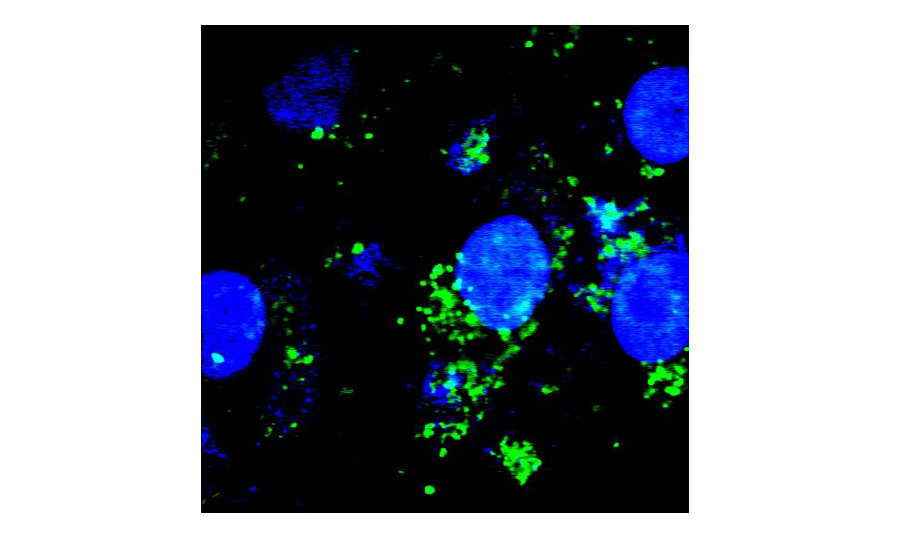

Whether the drug particle is correctly uptake by the target cell is critical evidence in pharmacodynamics. Through the optical sectioning capability of JadeBio, we can easily indicate the uptaking when showing the overlapped images once we label the cell and the drug particle in different colors. Furthermore, through high-resolution imaging of JadeBio, we can investigate which organelle is interacting with the drug particles.